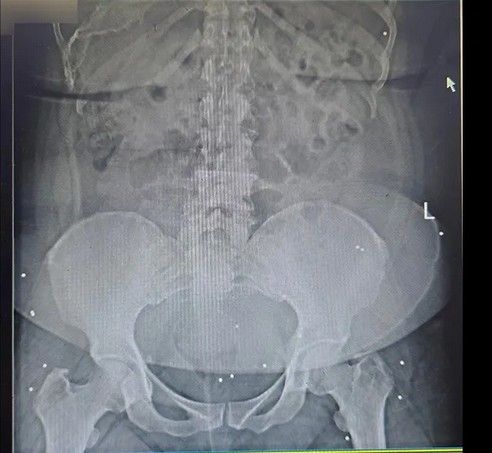

شلیک به اندامهای حیاتی

تصاویر رادیوگرافی و سیتیاسکن نشان میدهد اندام حیاتی تعداد زیادی از معترضان هدف شلیک ماموران امنیتی و نظامی قرار گرفته است. گردن، قفسه سینه، شکم، ستون فقرات و ناحیه تناسلی نقاطی هستند که به کرات هدف تیرهای ساچمهای و گاهی جنگی قرار گرفتهاند. همچنین تعداد زیادی از معترضان تنها از یک ناحیه هدف قرار نگرفتهاند؛ در یکی از موارد تیرهای ساچمهای در سر، گردن، کتف، قفسه سینه، پهلو و لگن فرد بستری دیده میشود. این موارد میتواند حاصل شلیک بیش از یک بار به سمت این معترض باشد. کیانا کثیری در این مورد میگوید که برخی آسیبهای واردشده به این معترض «دائمی» است و تا پایان عمر همراه او خواهد بود.

برخی از معترضان نیز با گلوله جنگی و به شکل مشخص از ناحیه اندام حیاتی هدف قرار گرفتهاند. در یکی از تصاویر رادیوگرافی گلوله یا ترکش در قفسه سینه و در ناحیه ریه مجروح دیده میشود، در تصویری دیگر گلوله جنگی در ناحیه تناسلی یک مرد قرار دارد و در موردی دیگر گلوله در نزدیکی ستون فقرات بیمار ثابت مانده است. کیانا کثیری در مورد عکس آخر میگوید: «در این عکس دو نوع آسیب را مشاهده میکنیم. یکی اصابت ناحیه پشت با گلوله جنگی، بر اساس ورود و قرار گرفتن گلوله به نظر میرسد که گلوله از بالا شلیک شده و آسیب دوم شکستگی سه مهره کمری،Lumbal Columna است که نیاز به ترمیم با فیکسیشنهای ارتوپدی داشته است.»